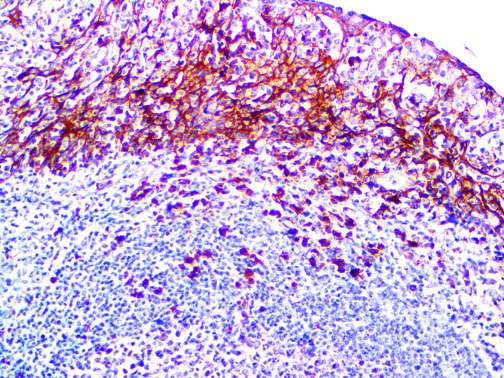

The first cytokines released are interleukin 1β (IL-1β) and tumor necrosis factor-α (TNF-α), which attract a variety of circulating white blood cells (WBCs) to the infection site, including neutrophils, monocytes, macrophages, and natural killer (NK) cells. This response, along with the antipathogenic chemicals released by these cells (i.e., complement), comprise the innate immune response. These cells directly attack the invading pathogen and also release additional cytokines, chief among them interleukin-1 and 6 (IL-6). IL-6 is essential for invoking the adaptive immune response, which calls T-cells, B-cells, and T helper (Th) cells to the infection site. IL-6 also stimulates further recruitment, proliferation and activation of macrophages.

It is the ICU physician who is most likely to witness one of the deadliest manifestations of the abnormal immunological response, the cytokine storm syndrome (CSS). This response is also referred to by some as the cytokine release syndrome (CRS). CSS is characterized by continuous activation and expansion of macrophage and lymphocyte populations, which secrete large amounts of cytokines, causing the cytokine storm. This massive cytokine release is akin to hemophagocytic lymphohistiocytosis (HLH) disease, a syndrome characterized by initial unchecked and persistent activation of cytotoxic T lymphocytes and NK cells.

Clinical and laboratory manifestations of HLH include fever, enlarged liver and/or spleen, neurologic dysfunction, coagulopathy, liver dysfunction, cytopenias (i.e., low levels of erythrocytes, leukocytes, and/or platelets), hypertriglyceridemia, hyperferritinemia, hemophagocytosis, and eventually diminished NK cell activity as the immune system becomes progressively paralyzed. HLH can be familial (primary HLH) or secondary to another disease process (sHLH), such as rheumatic disease, in which it is referred to as macrophage activation syndrome (MAS, characterized by elevated ferritin).